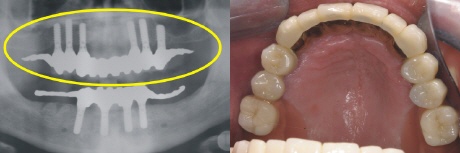

Implantation

Sechs strategisch günstig positionierte Implantate wurden im Oberkiefer eingebracht, um nach der Einheilung optimalen Halt für die Prothese zu gewährleisten (gelber Kreis im Röntgenbild).